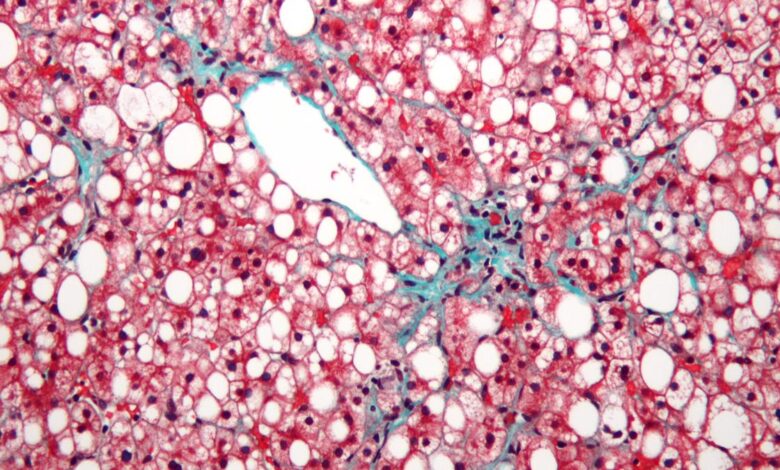

Mitdní játra doslova znamenají přebytečný tuk, který se ukládá v játrech. Jak se tento tuk staví, játra začne otok a postupem času ztrácí schopnost správně fungovat, což vede k různým zdravotním problémům. Hlavní příčinou je nesoulad mezi kaloriemi, které konzumujeme, a kaloriemi, které hoříme. Když jíme více mastných a kalorií hustých potravin-jako jsou zpracované potraviny, červené maso, smažené předměty a potraviny bohaté na olej-a nespálíme dostatek kalorií fyzickou aktivitou, přebytky kalorií se přeměňují na tuk a to se začne nahromadit v játrech.

Zpočátku mohou být usazeniny tuku v játrech malé a neškodné, ale pokud přetrvávají nezdravé návyky, tato depozity se postupně hromadí na nebezpečnou úroveň, což má za následek mastné onemocnění jater. Hlavními přispěvateli do této podmínky jsou nezdravá strava, sedavý životní styl a konzumace více kalorií než tělesné spálení. Aby se zabránilo a dokonce potenciálně zvrátilo mastné onemocnění jater, je nezbytná komplexní modifikace životního stylu, která se zaměřuje na stravu a fyzickou aktivitu.